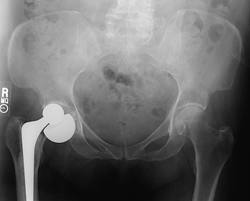

COMPLICATIONS OF HIP REPLACEMENT SURGERY

Unfortunately, even the most minor of surgical operations carries some risk of complications occurring. Hip replacement surgery is very successful, and complications are relatively uncommon, considering the complexity of the procedure.

Loosening of the prosthesis from the bone

is the most important long-term problem. How long the bond will last depends on a number of factors.

Dislocation of the hip replacement

occurs in a small percentage of patients regardless of how good your surgeon is (some surgeons report as high as 4%). With the Anterior Approach or the Gluteal Split techniques of hip replacement, or the use of a large femoral head the risk of dislocation is greatly reduced, although it can still occur. Dislocation means that the metal ball slips out of the plastic socket. In the first six weeks after the surgery, the ball is only held in the socket by muscle tension. During this time, before scar tissue forms around the ball, and before muscle strength returns, the hip is more likely to dislocate.